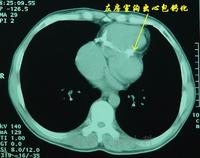

5.CT檢查 最初的CT掃描受到生物學運動的影響,現代CT檢查裝置克服了上述因素等影響,明顯增加了有用的信息。雖然生物運動可能仍對心臟腔室部位的診斷有所影響,但對心包部位的診斷已能相當正確。

6.磁共振檢查 磁共振檢查的主要優點是能夠對任何平面進行掃描,提供心臟、大血管以及心包膜的圖像,不受放射線或靜脈內造影劑的影響。通過磁弛豫時間對組織特徵的潛在分辨能力,優於CT和超聲心動圖。但無論CT或磁共振,對組織定性均是困難的,從總體來看,磁共振在定位或定性能力上均優於CT。